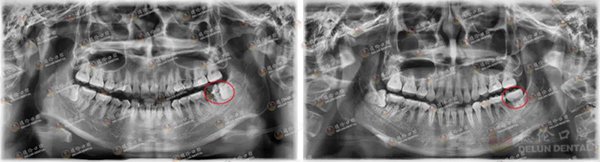

朱女士矫正前(左)与矫正中(右)对比图。朱女士希望通过矫牙将牙齿排列整齐、改善面型,并关掉明显的牙缝

庄女士矫正前(左)与矫正中(右)对比图。庄女士拔除了一颗严重蛀掉无保留价值的残根后开启矫牙之旅。李医生将庄女士的阻生智齿扶正前移,代替那颗被拔掉的残根